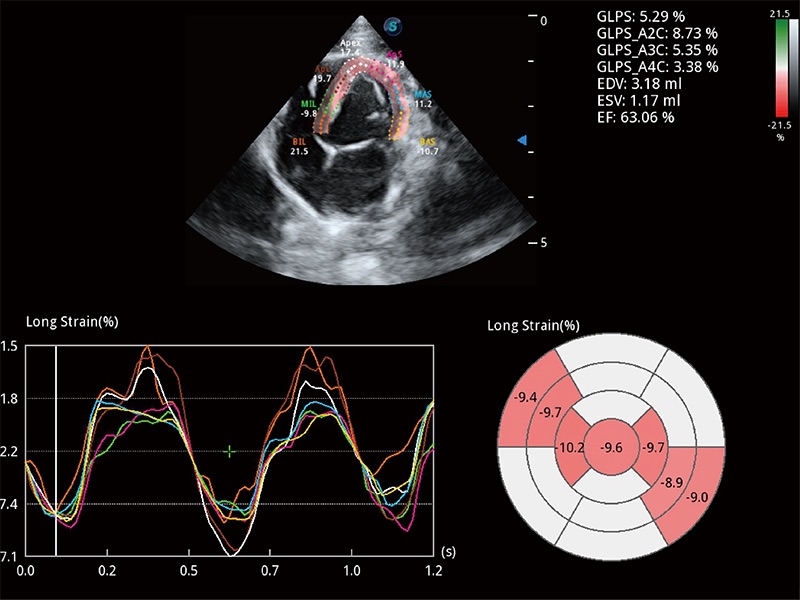

• MQA 心肌定量分析

通过心肌识别技术与二维斑点追踪技术相结合,对心脏的超声图像进行量化分析。计算心肌17个节段的应变、应变率、速度、位移等,并通过牛眼图的形式进行呈现。

• Auto EF 心内膜自动描迹

能够基于左心室壁追踪和辛普森法,自动计算射血分数,支持多个可移动点描迹,与手动测量相比,极大节省了动物医生的时间和精力。

(犬)四腔心MQA